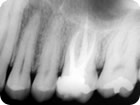

Retratamento Endodôntico

Retratamento Endodôntico 2